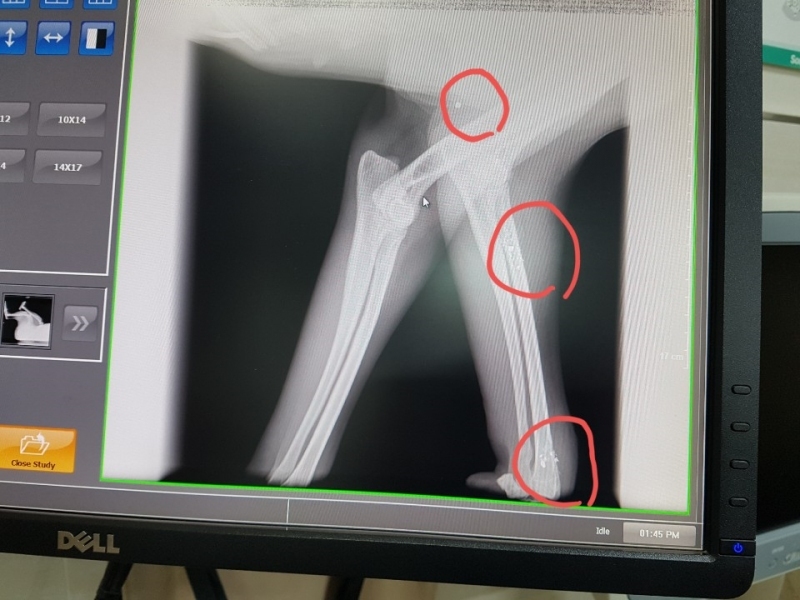

¿À´Ã ¼º³²¿¡ Àִ µ¿¹°º´¿ø¿¡ °¡¼­ ¿¢½º·¹À̸¦ Âï¾îº» °á°ú

½ÇźÀÌ ¿©·¯¹ß ¹ÚÇôÀִµ¥  ¼ö¼úÀ» ¸øÇÏ°í ¸Ô´Â°ÍÀº Àß ¸ÔÀ¸´Ï

ÁöÄѺ¸ÀÚ°í ÇÕ´Ï´Ù,

°ßÀÌ ¸Ô´Â°Íµµ À߸԰í Ȱ¹ßÇѵ¥  ¿ÞÂÊ ¹ß¸ñÀ» ¾²Áö ¸øÇÕ´Ï´Ù,

¿ÞÂÊ´Ù¸® ¹ß¸ñ¿¡ ½ÇźÀÌ ¹ÚÇôÀִµ¥ »À¸¦ ¸Â°í ½ÇźÀÌ ºÎ¼­Áø ´À³¦ÀÔ´Ï´Ù,

±×ÂÊÀº Àε¥°¡ Àִµ¥  Àε¥°¡ ²÷¾îÁø°Í  °°¾Æ¿ä,

2¿ù 15ÀÏ ±¤Áֽà ÃÊ¿ù¸é¿¡ ÀÖ´Â À̼ٵ¿¹° º´¿ø¿¡¼­ Á¤¹Ð ¿¢½º·¹ÀÌ ÃÔ¿µ ÇßÀ¾´Ï´Ù,

´Ù¸®¿¡ ºÎ¼­Áø ¿±ÅºÀº »À¿¡ ¸Â¾Æ »À°¡ ±ÝÀ̰¡°í ¾à°£Àº »À¼ÓÀ¸·Î µé¾î °¬´Âµ¥

ºÎ¼­Áø ¿±ÅºÀ» »©´Â ¼ö¼úÀº ºÒ°¡´ÉÇÏ°í µ¿¹°Àº »ç¶÷ÇÏ°í ´Þ¸® ÀÌ»óÇÑ ¹°Ã¼°¡ µé¾î¿À¸é

Ç×ü°¡ »ý°Ü¼­ ¹°Ã¼¸¦ ¿¡¿ö½×°í ¸·ÀÌ »ý°Ü  ´õ´Â ÀÌ»óÀÌ ¾ø°í »ç´Âµ¥´Â ÁöÀåÀÌ ¾ø´Ù°í ÇϽôõ±º¿ä.

¿±ÅºÀÌ ½ÉÀå, Æó, ³»Àå±îÁö µé¾î°¡¸é À§ÇèÇѵ¥ ¸ö¼Ó¿¡ ¹ÛÈù°ÍÀº

¸Ô±â¸¸ ÀßÇÏ¸é »ì¼ö ÀÖ°í 3ÁÖ ÈÄ¿£ °ÅÀÇ Á¤»ó±îÁö ¿À´Ï±î ½Ã°£À» °¡Áö°í

±â´Ù·Á º¸¶ó´Â  µ¿¹°º´¿ø¿øÀå´ÔÀÇ Á¾ÇÕÀûÀÎ ÆÇ´ÜÀÔ´Ï´Ù,